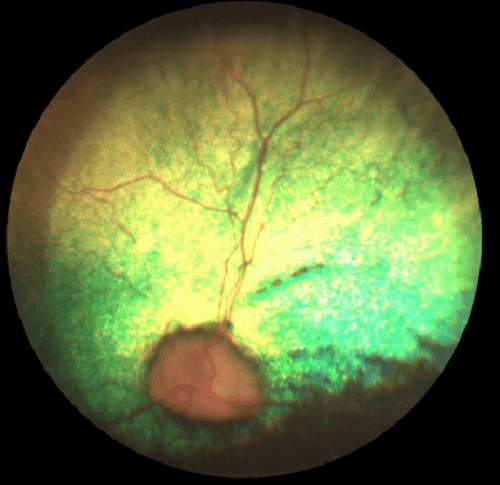

Progressive Retinal Atrophy, GR PRA2

This form of PRA for the Golden Retriever is one of several that can be tested for. The signs of GR PRA1 are typical of the late-onset forms of the disease. Age of diagnosis is most often around 5 years, but there is variation across the breed. Dogs typically experience night blindness leading to reduced sight even in bright conditions. There are known to be more than one gene mutations that cause PRA(prcd) in the Golden Retriever. Any test for GR PRA 2 can only confirm for the mutation, or not, in this specific form.

Most PRA cases in the Golden Retriever (GR) are clinically indistinguishable from other forms of PRA. The mode of inheritance appears from pedigree information to be autosomal recessive. While the age of diagnosis is most commonly at a relatively late age of approximately 5 years there is a great deal of variation within the breed. There are known to be more than one gene mutations that cause PRA(prcd) in the Golden Retriever.